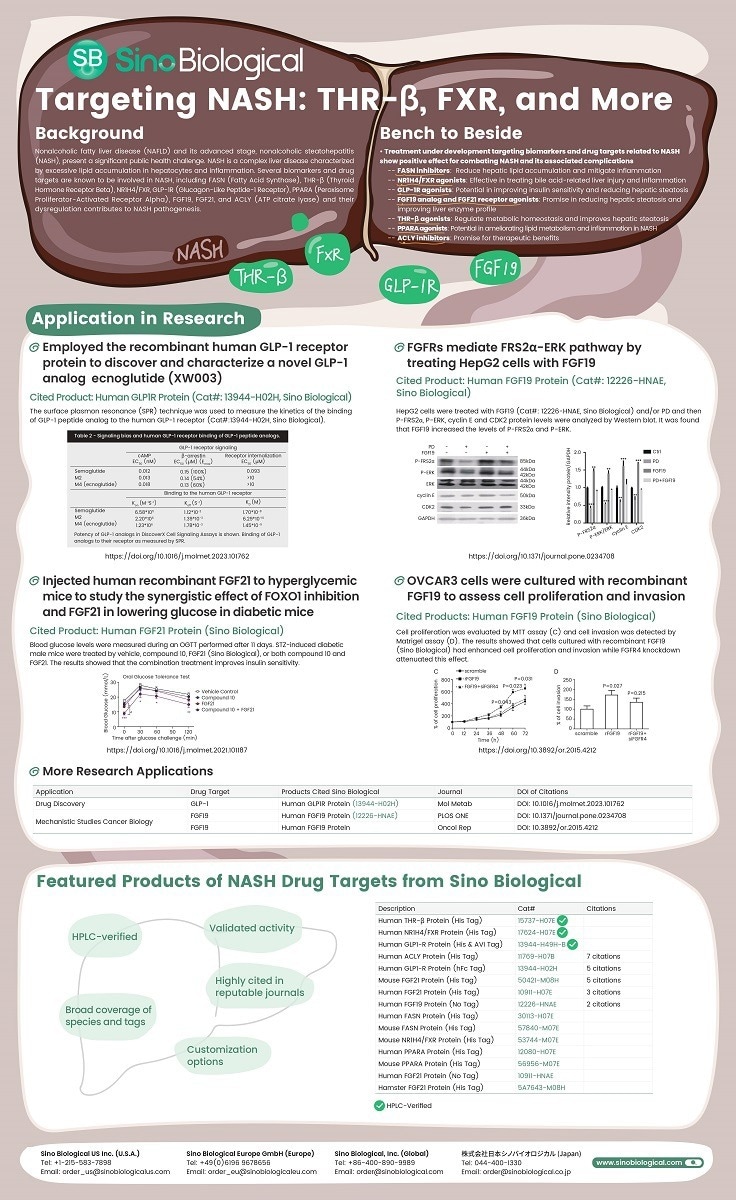

As of August 2023, there is no FDA-approved treatment for this condition. Various biomarkers and drug targets, such as Fatty Acid Synthase (FASN), Thyroid Hormone Receptor Beta (THR-β), NR1H4/FXR, Glucagon-Like Peptide-1 Receptor (GLP-1R), Peroxisome Proliferator-Activated Receptor Alpha (PPARA), FGF19, FGF21, and ATP citrate lyase (ACLY), are known to play a role in NASH development due to their dysregulation.

Clinical trials of the THR-β agonist Resmetirom have shown promising results for treating NASH. Ongoing research is also exploring FASN inhibitors to reduce lipids, NR1H4/FXR agonists to address bile acid-related injuries, GLP-1R agonists to improve insulin sensitivity, and FGF19/FGF21 analogs to reduce hepatic steatosis. ACLY inhibitors also show potential in NASH treatment.

Sino Biological provides recombinant NASH-related drug targets to support drug discovery and study the interactions between these targets, offering valuable insights for developing innovative NASH therapies and addressing associated conditions like diabetes.

Image Credit: Sino Biological Inc.

Addressing the complex development of NAFLD and NASH is increasingly important due to their growing prevalence. Several biomarkers and drug targets, including FASN, THR-β, GLP-1R, PPARA, FGF19, FGF21, NR1H4/FXR, and ACLY, provide promising avenues for tackling NASH and its related issues.

Inhibiting FASN aims to reduce fat buildup in the liver and reduce inflammation. Preclinical studies show the effectiveness of NR1H4/FXR agonists like Tropifexor and Nidufexor in addressing liver damage and inflammation related to bile acids. GLP-1R agonists like Semaglutide and Liraglutide can potentially improve insulin sensitivity and reduce liver fat.

FGF19 analog (Aldafermin) and FGF21 receptor agonist (Pegbelfermin) also promise to reduce liver fat and improve liver function. In preclinical studies, the THR-β agonist Resmetirom helps regulate metabolic balance and improves liver fat buildup.

PPARA agonists can potentially improve lipid metabolism and reduce inflammation in NASH. Ongoing investigations into ACLY inhibitors like Bempedoic acid hold promise for their therapeutic benefits.

These ongoing clinical trials and research efforts offer hope for innovative and effective therapies to combat NASH and its associated complications, including diabetes.